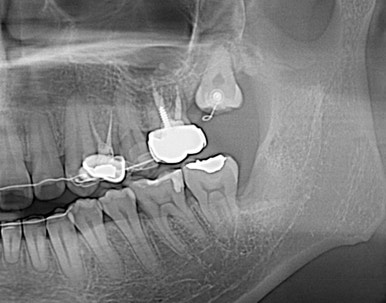

Case details

사랑니 교정

사랑니를 교정치료를 통해 어금니로 사용하는 케이스